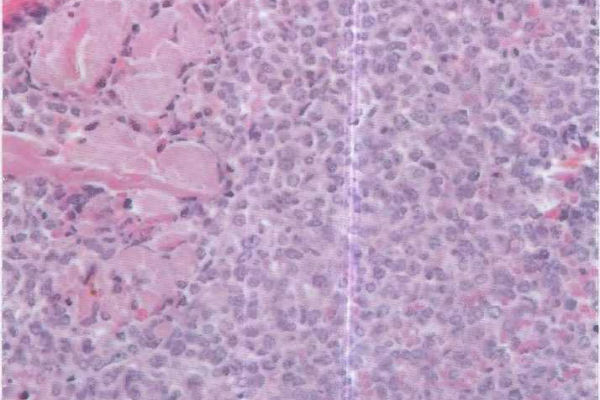

Атипичные клетки

При пременопаузе нехватка половых гормонов может заставить перерождаться клетки яичников и других органов, мутировать. Организм не способен контролировать атипичные клетки. Здоровое тело устроено так, что эти мутанты постепенно саморазрушаются, но при неблагоприятных условиях начинают расти и становятся злокачественными.

Онкомаркеры – это опухолевые выделения, появляющиеся в крови женщины, заболевшей онкологией, в состав которых входят белки, гормоны, обменные продукты и антигены.